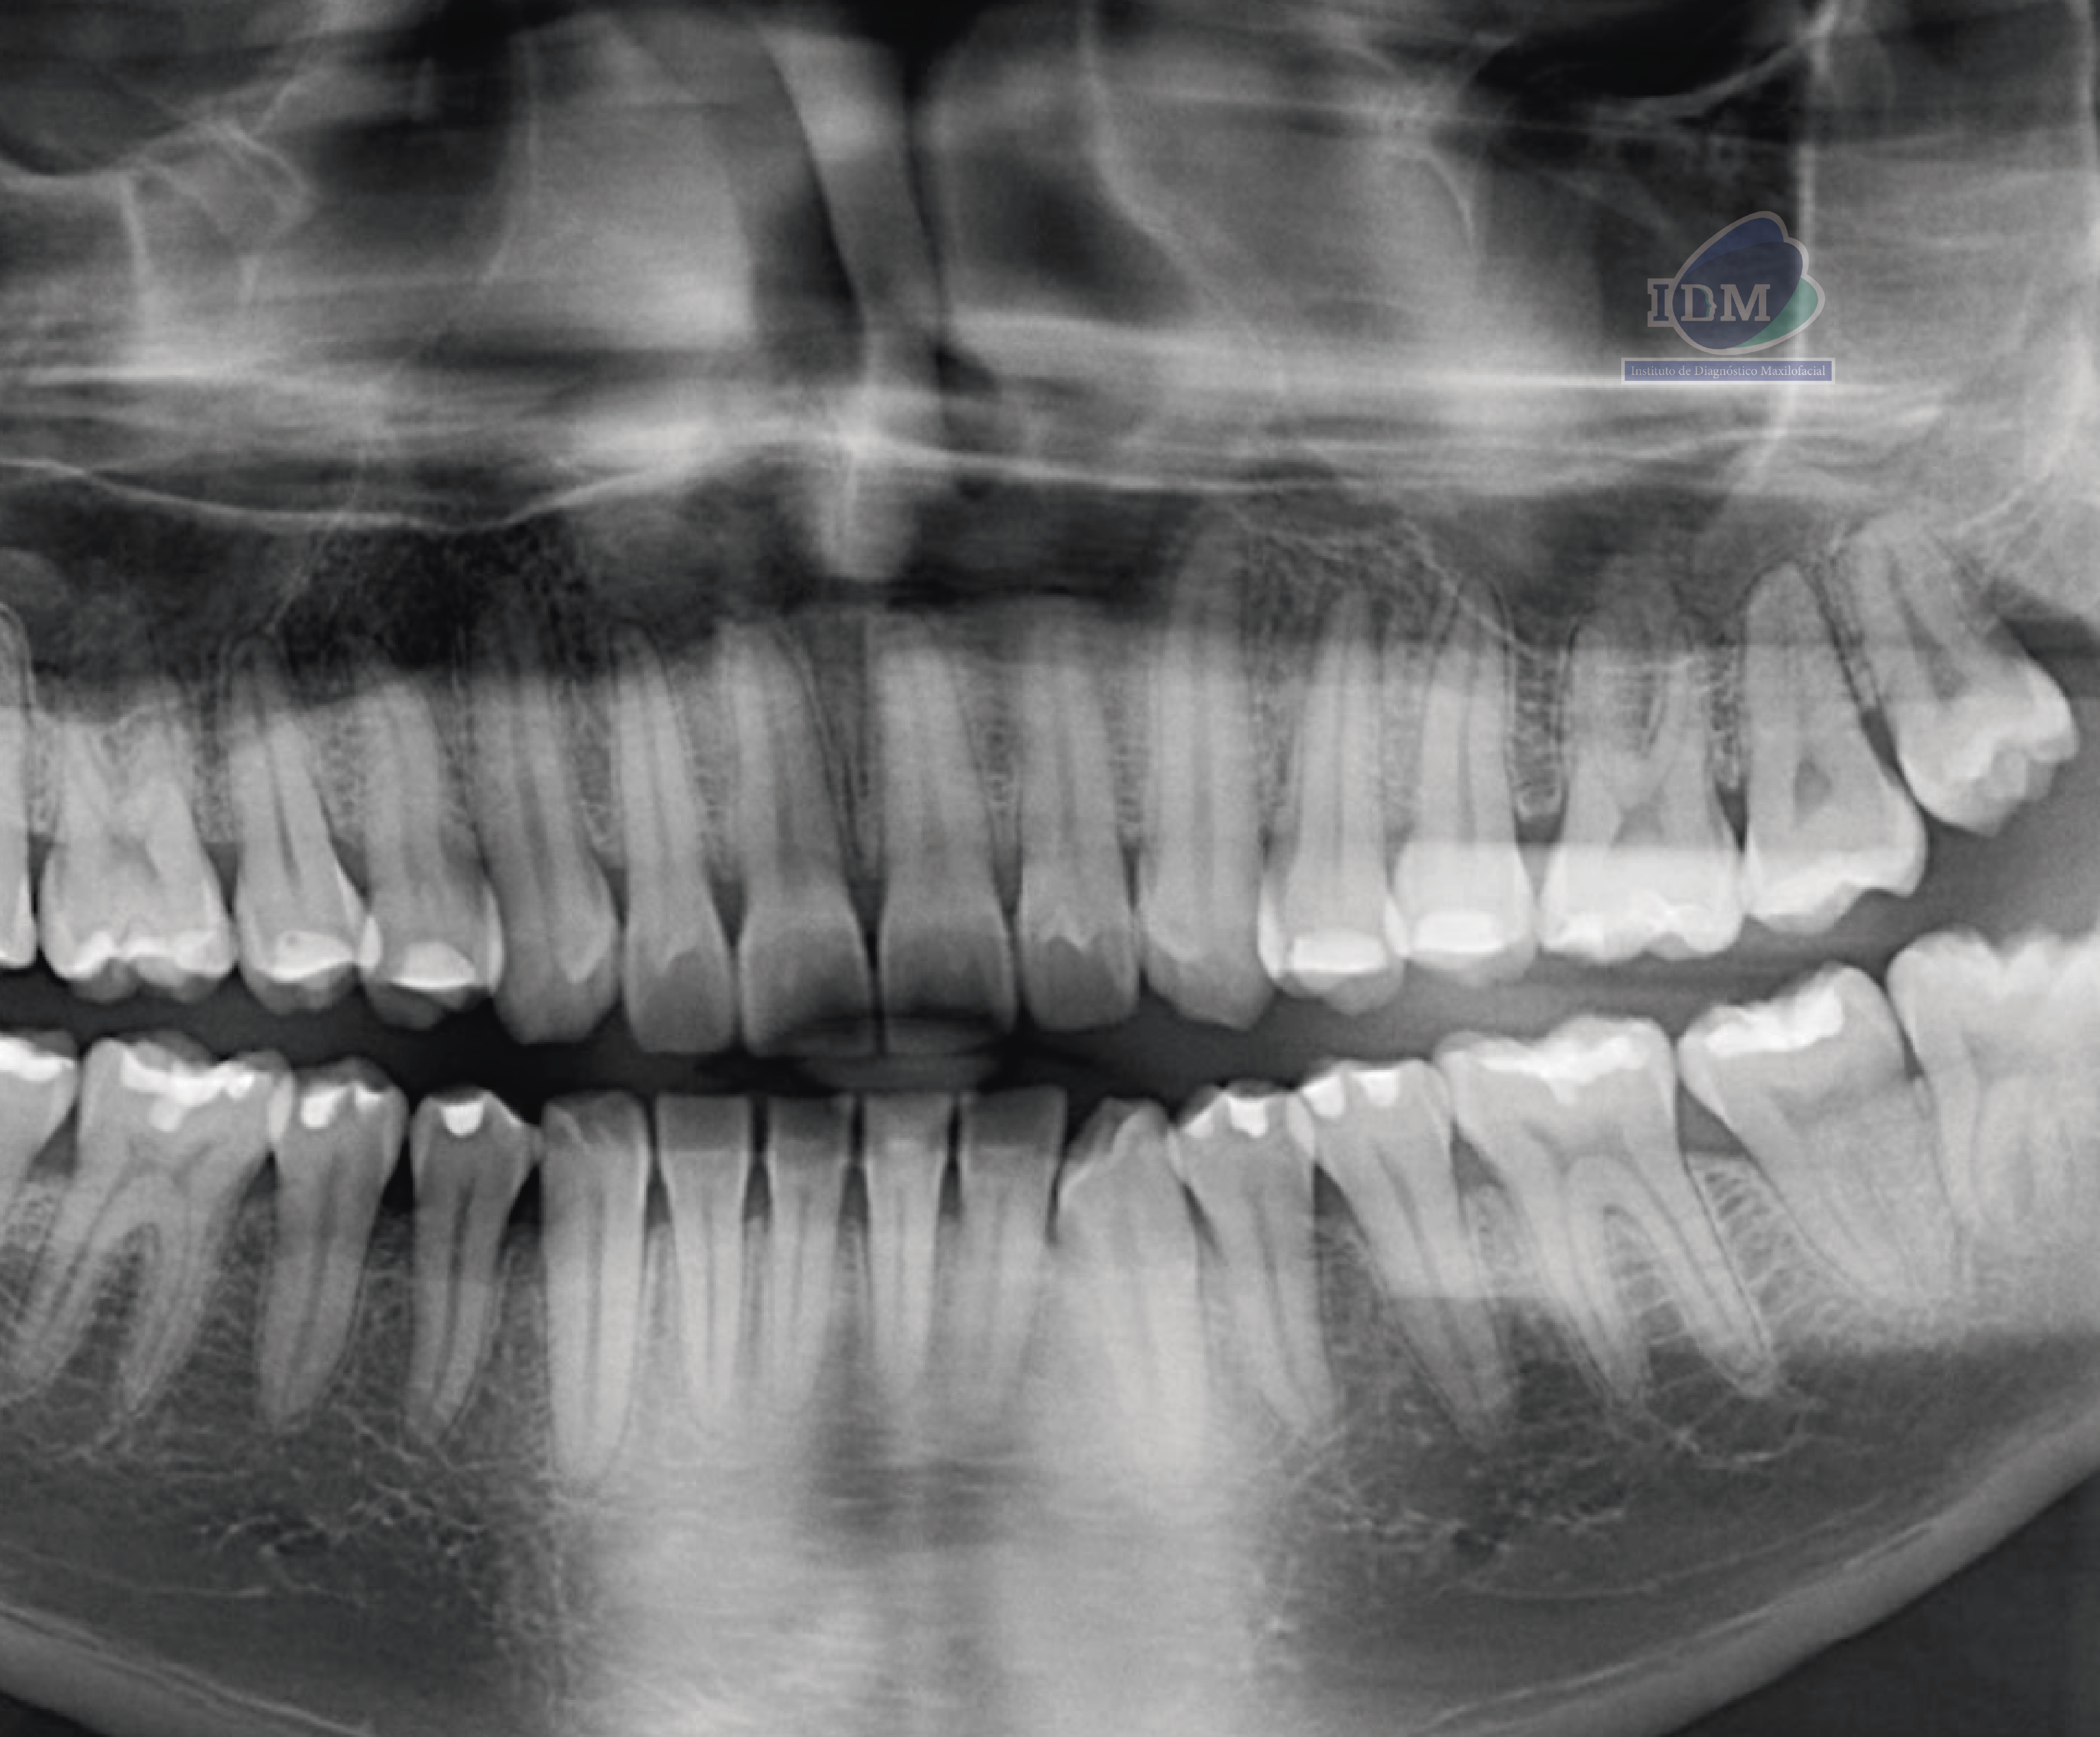

Paciente masculino de 25 años de edad acude al Instituto para una tomografía de macizo facial para la colocación de ortodoncia, a la evaluación de la radiografía panorámica se observa la neumatización de ambos senos

maxilares, atrición de piezas dentarias anterosuperiores y anteroinferiores, múltiples restauraciones coronarias, la retención de las piezas dentarias 38 y 48, ambas en relación con el borde anterior de la rama mandibular. Además, llama la atención una imagen radiopaca de forma redondeada proyectada sobre la porción radicular de la pieza 17.

Radiografia Panorámica

A la evaluación de la tomografía computarizada (en cortes axiales y transaxiales) se puede observar la presencia de una pieza supernumeraria de tamaño reducido (microdiente)localizada por lingual de la pieza 18 y que al evaluar los cortes tangenciales se aprecia una discreta dilaceración hacia distal.